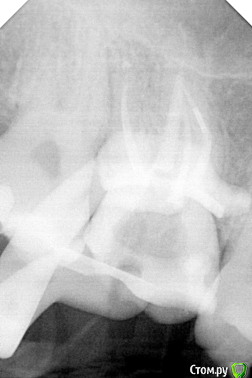

АнтонТЛТ Опубликовано 17 июля, 2020 Поделиться Опубликовано 17 июля, 2020 Первый раз такое, надо переходить на другие иглы))Как на фото лучше не брать))) Ссылка на комментарий

АнтонТЛТ Опубликовано 17 июля, 2020 Автор Поделиться Опубликовано 17 июля, 2020 Самое обидное было то, что это было последнее промывание перед пломбировкой кк. Ссылка на комментарий

Kolchanov Опубликовано 17 июля, 2020 Поделиться Опубликовано 17 июля, 2020 Аналогично. Еще лет семь назад. И не заметил. Начал сушить пинами, а не лезет. Смотрю все инструменты. Целые! На снимке в канале обломок. Блииин! Стал доставать, благо недалеко, а там труба. Эндонидл, ё-моё. 10ка н-файл через и вытащил. С тех пор отламываю всё. И концы, и скосы. Ничего никуда еще шприцем не вывел. При активации уз или гуттаперчей - бывает. Или ротари иногда протолкнёт. Ссылка на комментарий